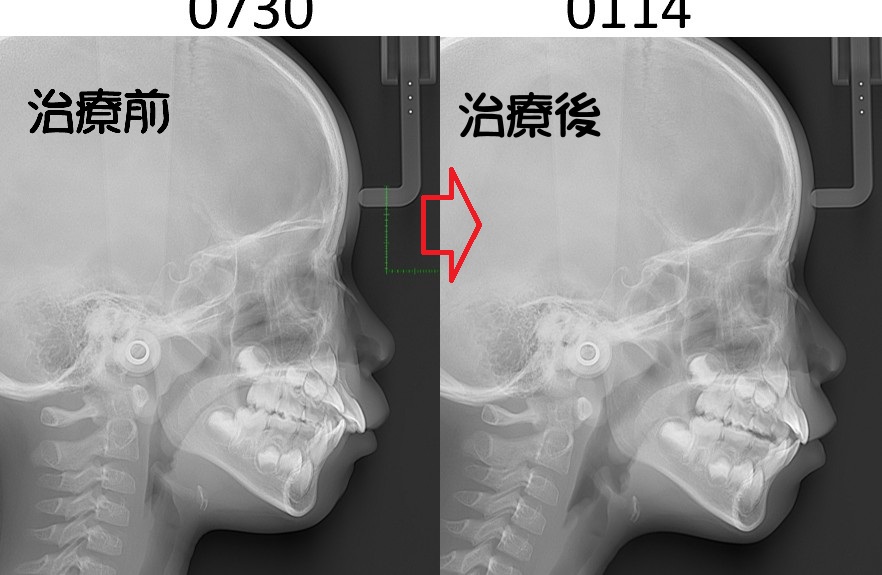

①レントゲン写真:頭部X線規格写真(セファログラム)など検査をしている

患者さんの顎顔面の成長バランスや成長方向、量の予測をするために不可欠な検査です。